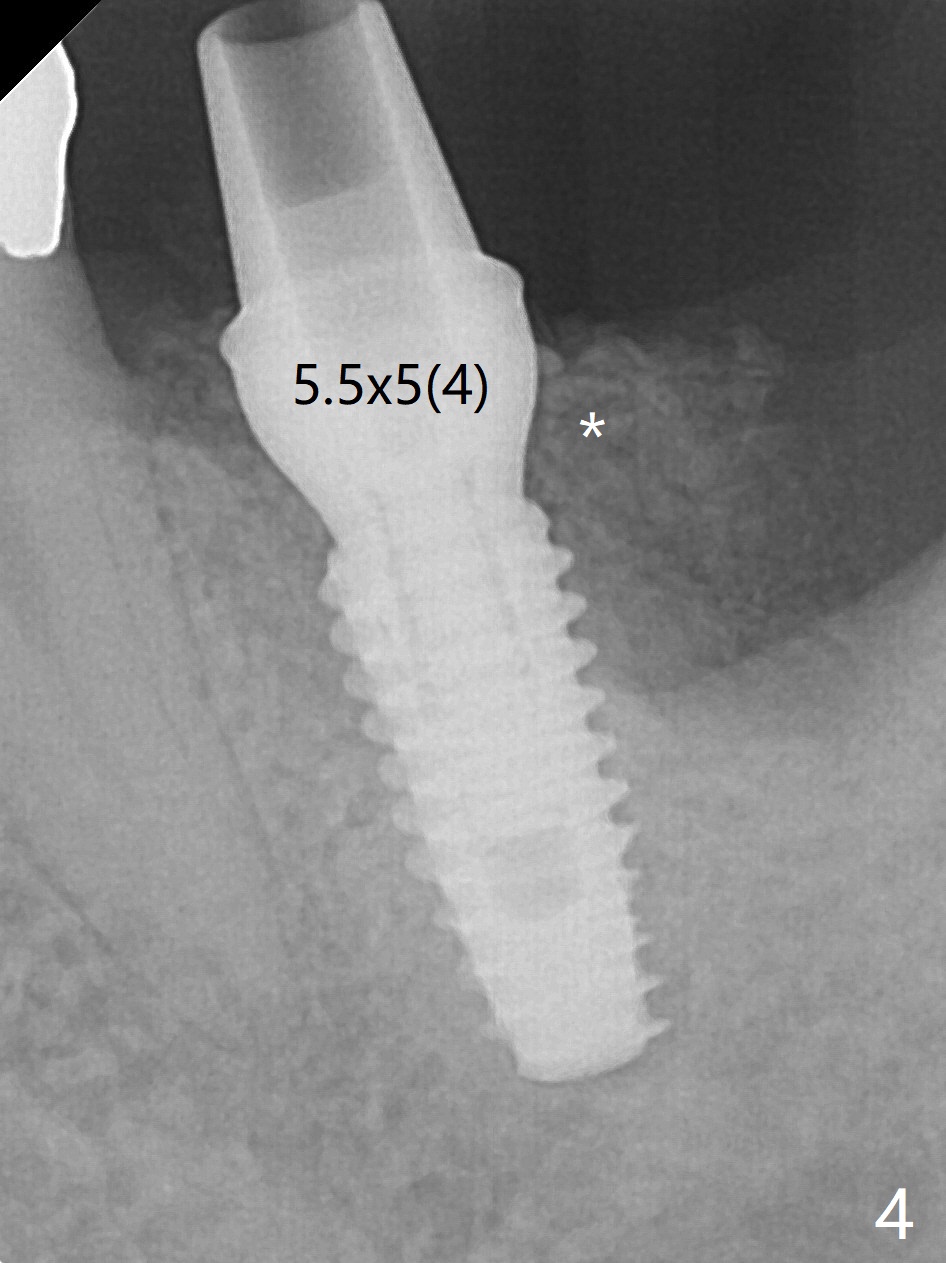

The guide does not arrive when the tooth #19 is extracted. Osteotomy is initiated free hand in the mesial socket as planned, slightly lingual, for 11.5 mm (Fig.1). Following sequential osteotomy, a 4.5x10 mm implant is placed subcrestal septally (Fig.2 S) and 2.3 mm from the neighboring apex (Fig.4). A 5.5x5(4) mm abutment is placed immediately and allograft is placed in the remaining sockets (Fig.4 *). An immediate provisional is fabricated to keep the graft in place (Fig.5 P; the most secure socket preservation).